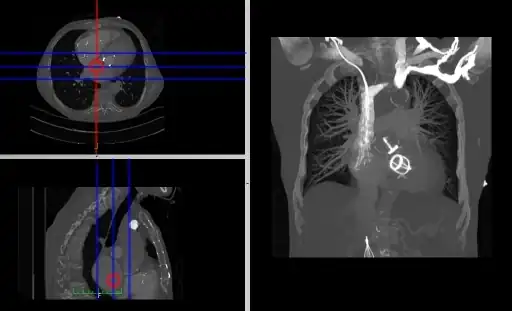

- Composite MPR Display

- Coronal and sagittal reconstructions are referred to as Orthogonal MPRs because the perspectives generated are from planes of image data which are at right angles to each other. Composite MPR displays can be generated so that linked cursors or crosshairs can be used to locate a point of interest from all three perspectives, as illustrated in these images:

![]() |

- This form of image presentation is sometimes referred to as a TCS display – implying the viewing of Transaxial, Coronal and Sagittal slices. It can be combined with the slice projection methods we discussed earlier, as illustrated in the two sets of images below, where the blue lines highlight the limits of the coronal projections:

- Here the plane can be defined in, say, the axial images (red line, top left) and a maximum intensity projection (the limits used are highlighted by the blue lines), for example, can be displayed for the reconstructed plane (right). This technique is useful when attempting to generate perspectives in cases where the visualization of three-dimensional structures is complicated by overlapping anatomical detail.